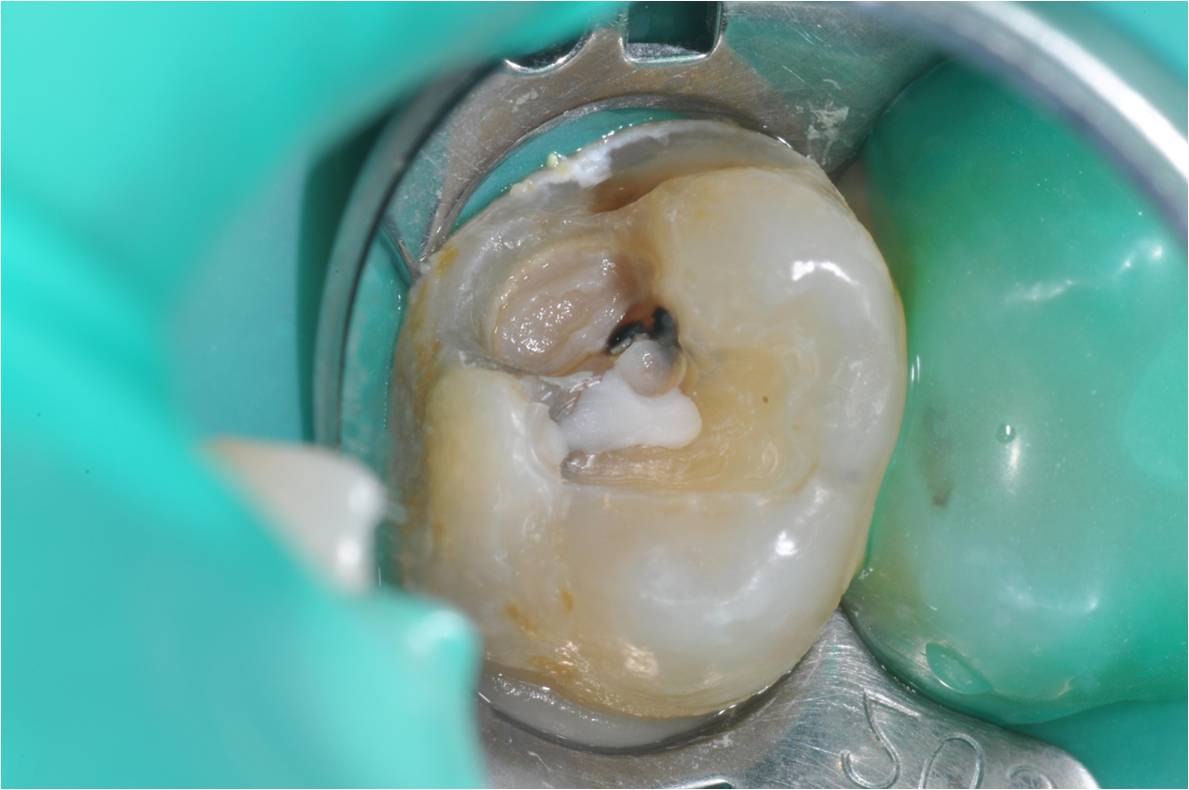

上椽皮障,顯微鏡下,崁體修形